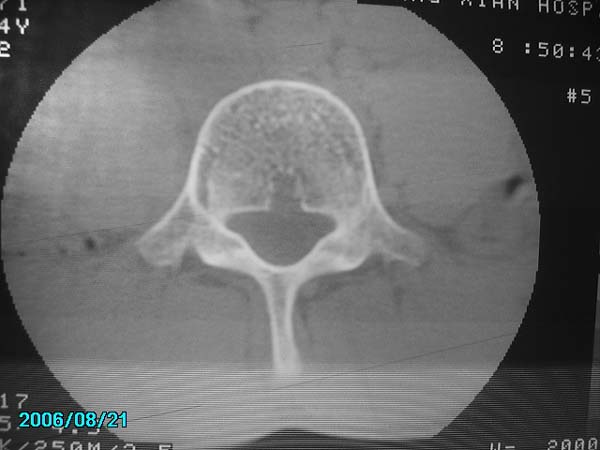

除有第3-5腰椎椎体后缘中央血管沟显示外,诸椎间盘比较正常。我也象13081830109战友那样看见了指纹,呵呵。

不会就是要我们看椎间盘吧?